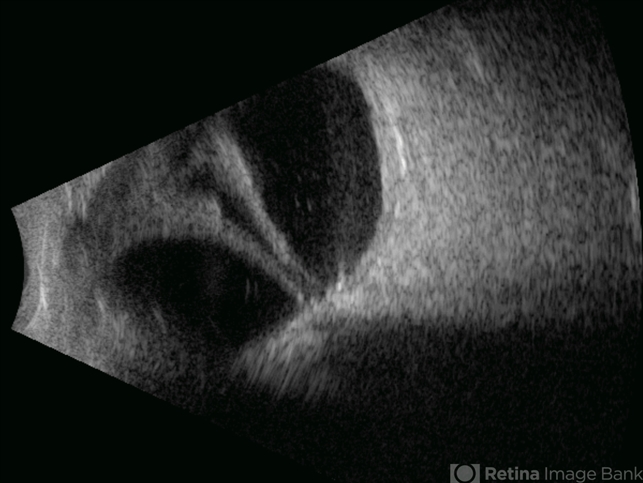

- open funnel RD, Retina detachment

- Gustavo U. Fonseca Aguirre, Hospital Conde de Valenciana, Ciudad de México

Ultrasonography device

- This B-mode longitudinal ultrasound scan demonstrates a long-standing rhegmatogenous retinal detachment, showing a characteristic open funnel configuration. The findings are consistent with chronic retinal detachment.